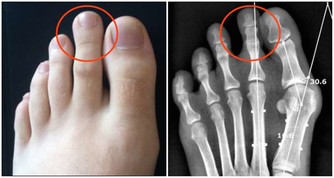

過敏表現常在接觸過敏原半小時至數小時後出現。一般表現如下:煩躁、心慌、胸悶、咽部不適、視物模糊、疲勞、易激惹、緊張、自控力下降、忍耐力下降、情緒失控、皮膚潮紅、紫癜、皮疹、耳道濕潤、鼻塞、鼻涕、鼻塞、噴嚏、眼瞼浮腫、腹痛、腹瀉、多汗、咳嗽,哮喘,呼吸淺快、血壓降低、關節冷痛等等。可見於多種過敏性疾病(如過敏性哮喘、咳嗽、紫癜、皮炎、鼻炎)、一些易激綜合徵(比如腸易激,還有情緒易激等等)、濕疹、痛經、咽炎等等。